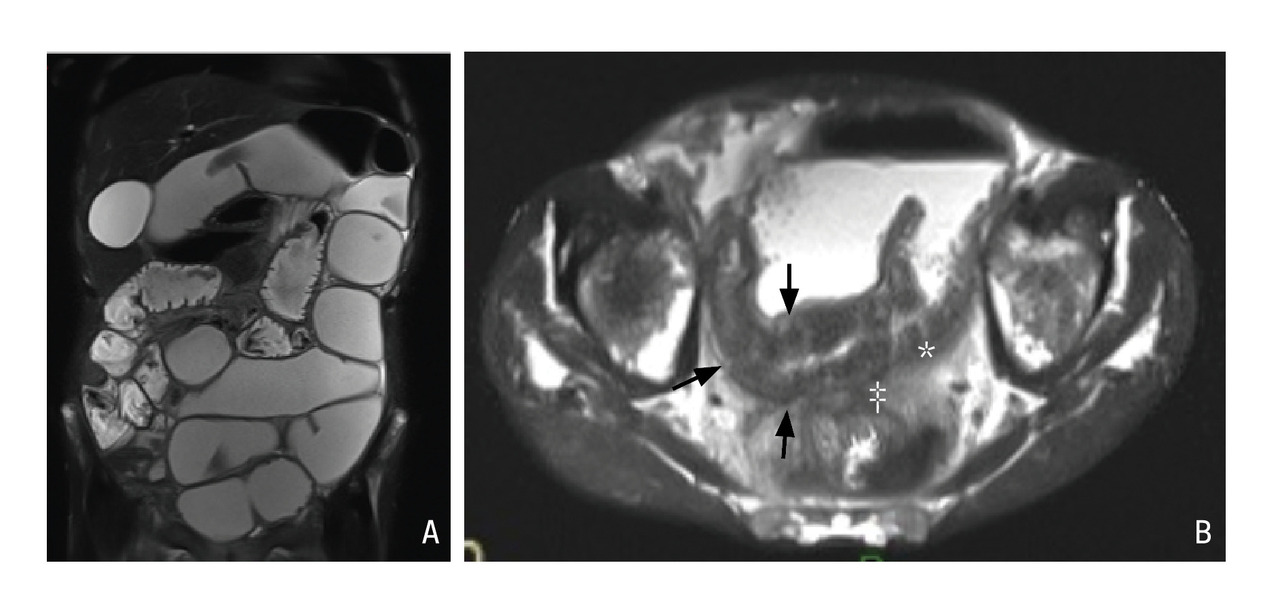

Témoins d’inflammation : œdème pariétal et lésions muqueuses

En pratique, les éléments les plus utiles pour l’évaluation de l’inflammation sont la recherche d’un hyper­signal T2, témoin d’un œdème de la paroi, et la recherche de lésions muqueuses, en par­ticulier d’ulcères ou de micro-abcès pariétaux (fig. 3).7

Comme à l’échographie, une hyperhémie ou un épaississement de la paroi au-delà de 4 mm sont considérés comme des signes d’inflammation pathologiques.7 Enfin, les séquences de diffusion facilitent le repérage des segments inflammatoires apparaissant en restriction de diffusion.